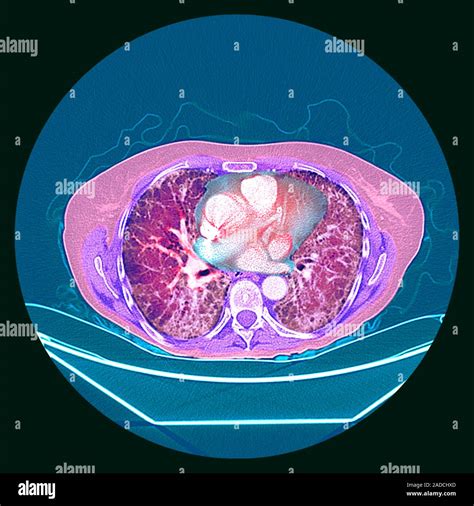

Receiving medical imaging results can often feel overwhelming, especially when terms like lung scarring on CT scan appear on your radiology report. Finding evidence of scarring—medically referred to as pulmonary fibrosis or interstitial lung abnormalities—can trigger anxiety, but it is important to remember that these findings are descriptive and require clinical context to be fully understood. A CT scan is a highly sensitive diagnostic tool that provides a detailed cross-sectional view of the lungs, allowing doctors to identify changes in the lung tissue that might not be visible on a standard chest X-ray. Understanding what this scarring means, why it happens, and what steps you should take next is the first step toward managing your respiratory health effectively.

When your doctor discusses lung scarring on CT scan, they are looking at specific patterns that tell a story about the lung’s history. Radiologists often use specific terminology to describe the appearance of these changes. Here is a simplified table of common radiological findings and their general implications:

Radiological Term What It Usually Implies

Reticulation A net-like pattern indicating mild thickening of the lung structure.

Honeycombing Clusters of cystic air spaces; often suggests advanced or established scarring.

Ground-Glass Opacities Hazy areas; these may indicate active inflammation that could be reversible, rather than permanent scar tissue.

Traction Bronchiectasis The pulling open of airways due to the contraction of surrounding scar tissue.